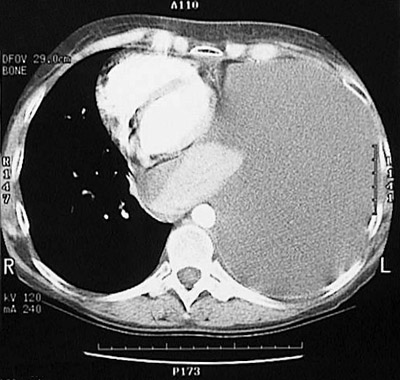

| This large pleural effusion seen with chest CT scan at lung density resulted from extensive pleural metastases from a breast carcinoma. The effusion fills the left chest cavity and displaces the heart to the right. On thoracentesis, the fluid was bloody, typical of the effusions associated with malignancies. |